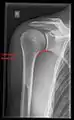

X-ray

Projectional radiography views of the shoulder include:

- AP-projection 40° posterior oblique after Grashey

The body has to be rotated about 30 to 45 degrees towards the shoulder to be imaged, and the standing or sitting patient lets the arm hang. This method reveals the joint gap and the vertical alignment towards the socket.[23]

CR. shoulay film.